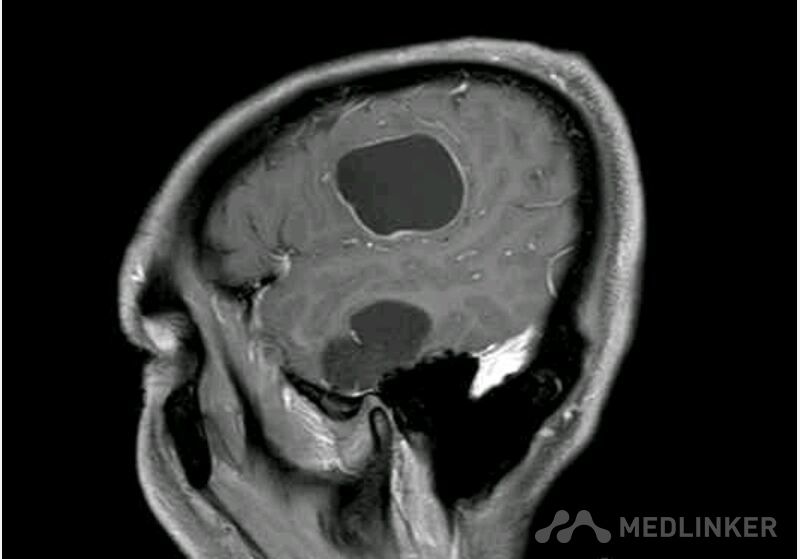

脑囊虫病高清影像资料分享

脑囊虫病经典资料